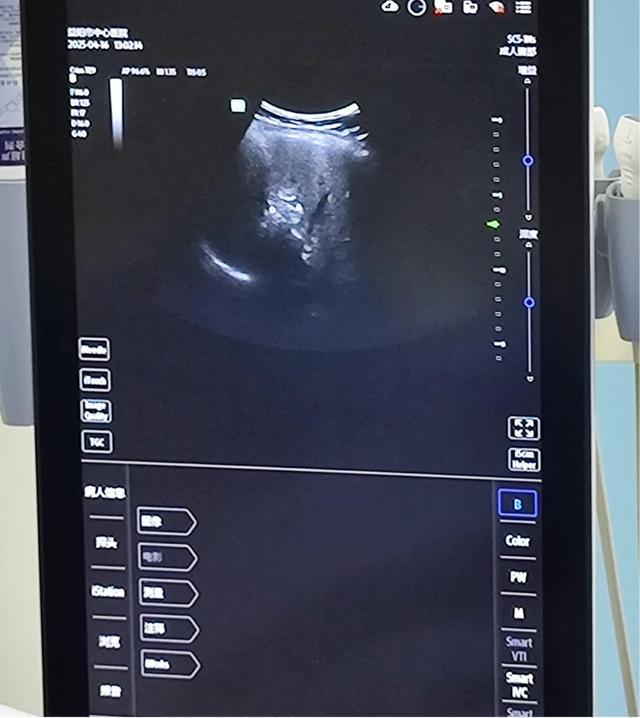

(术中B超实时影像)

4月16日上午10时,手术在局部麻醉下进行。肿瘤介入专家副主任医师陈恭让与主治医师姚晓艺主刀,陈恭让手持微波消融针,在B超引导下避开肝周肠管,沿预设路径穿刺至肝右叶病灶。当监测到肿瘤处于呼吸周期的“静止期”时,姚晓艺发出指令,实施消融。

随着微波发生器启动,直径3厘米的消融区域迅速覆盖转移灶,仪器显示中心温度达95℃,持续12分钟确保肿瘤细胞完全灭活。双定位技术通过“动态建模+实时校准”,使转移灶消融的完全率从75%提升至92%。